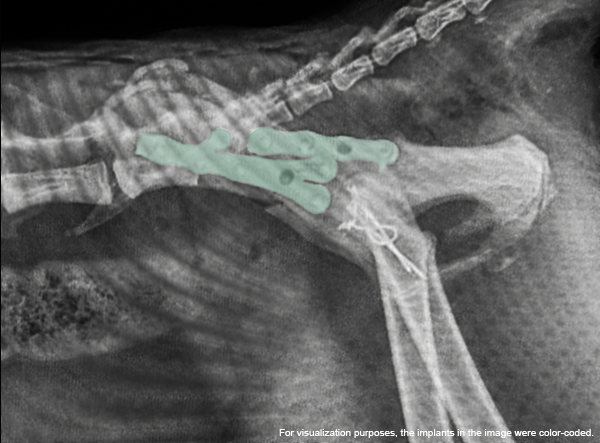

- LeiLOX 1.5 Y-Plate

Positioned on the ilium, the Y-Plate was used to stabilize the comminuted ilial fracture and restore acetabular alignment. The plate’s geometry allowed for secure multi-point fixation in challenging anatomy. - Twisted Straight Plate

A LeiLOX Locking 1.5 straight plate was carefully twisted and adapted to the curved contour of the ilium, providing additional stabilization of the ilial shaft. - Single Transarticular SI Screw

On the contralateral ilium (left side), a long cortical screw was placed across the SI joint into the sacrum to address the sacroiliac luxation. This achieved rigid fixation of the pelvis to the vertebral column.

Post-operative radiographs showed excellent alignment, secure implant positioning, and stable SI fixation. This multifaceted repair highlights the versatility of the LeiLOX system and the skill of the surgical team. The patient is recovering well with a positive long-term prognosis.